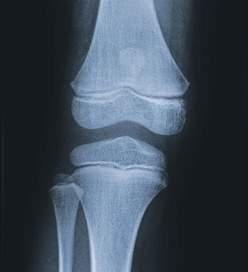

Опорно-рухова система людини дає

тілу, зумовлює його форму, забезпечує рух, а також

захист внутрішніх органів. Такі її компоненти, як кістки, хрящі, зв’язки, сухожилля та ін., утворені сполучною тканиною.

М’язи складаються з посмугованої м’язової та сполучної тканин. В опорно-руховій системі людини кістки є пасивною, а скелетні м’язи активною частиною, яка забезпечує рухи кісток.

Кістка — це основна структурна одиниця

скелета. Функціями кісток є забезпечення опори, руху